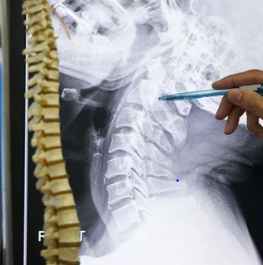

목디스크, 즉 경추 디스크는 경추의 추간판이 손상되어 인근 신경을 압박하는 질환입니다. 이로 인해 목 통증, 팔 저림, 손가락 무감각 등의 증상이 나타날 수 있습니다. 치료 방법은 증상의 정도와 개인의 상태에 따라 다르지만, 일반적으로는 물리치료, 약물치료, 주사치료 등 보존적 치료 방법이 우선적으로 고려됩니다. 만약 보존적 치료로 증상이 호전되지 않을 경우, 수술적 치료를 고려할 수도 있습니다. 중요한 것은 적절한 자세를 유지하고, 정기적인 운동을 통해 목과 등 근육을 강화하는 것입니다. 이는 목디스크의 예방 및 증상 완화에 도움이 될 수 있습니다. 또한, 장시간 같은 자세를 유지하는 것을 피하고, 필요시 전문가의 도움을 받는 것이 좋습니다. 오늘은 목디스크 증상과 치료방법에 대해 알려드리겠습니다.

목디스크, 즉 경추 디스크는 경추의 추간판이 손상되어 인근 신경을 압박하는 질환입니다. 이로 인해 목 통증, 팔 저림, 손가락 무감각 등의 증상이 나타날 수 있습니다. 치료 방법은 증상의 정도와 개인의 상태에 따라 다양합니다. 초기에는 물리치료, 약물 치료, 주사 치료 등 보존적 치료를 시도할 수 있으며, 증상이 심각하거나 보존적 치료로 호전되지 않을 경우 수술적 치료를 고려할 수 있습니다. 또한, 꾸준한 자세 교정과 목 근육을 강화하는 운동도 중요합니다. 목디스크 예방을 위해서는 장시간 같은 자세를 피하고, 정기적으로 스트레칭을 하는 것이 좋습니다.

목디스크, 또는 경추 디스크는 경추의 추간판이 손상되어 인근 신경이나 척수를 압박하는 질환입니다. 이로 인해 다양한 증상이 나타날 수 있는데, 가장 흔한 증상은 목 통증과 뻣뻣함입니다. 이 통증은 어깨, 팔, 손가락으로 방사될 수 있으며, 때로는 손의 저림이나 감각 이상을 동반하기도 합니다.

또한, 목디스크 환자는 두통을 경험할 수 있으며, 특히 뒷목에서 시작하여 머리 뒤쪽으로 퍼지는 형태로 나타납니다. 심한 경우에는 근력 약화나 운동 조정 능력 저하가 발생할 수 있으며, 이는 일상 생활에 큰 불편을 초래할 수 있습니다.

목디스크의 증상은 사람마다 다르게 나타나며, 일부 환자는 심각한 통증 없이 경미한 불편함만을 느낄 수도 있습니다. 그러나 증상이 지속되거나 악화될 경우, 의료 전문가와 상담하여 적절한 진단과 치료를 받는 것이 중요합니다.

치료 방법은 증상의 정도와 개인의 상태에 따라 다양하며, 물리 치료, 약물 치료, 주사 치료, 또는 수술적 치료가 필요할 수 있습니다. 건강한 생활 습관, 적절한 자세 유지, 정기적인 운동은 목디스크 예방에 도움이 될 수 있습니다.